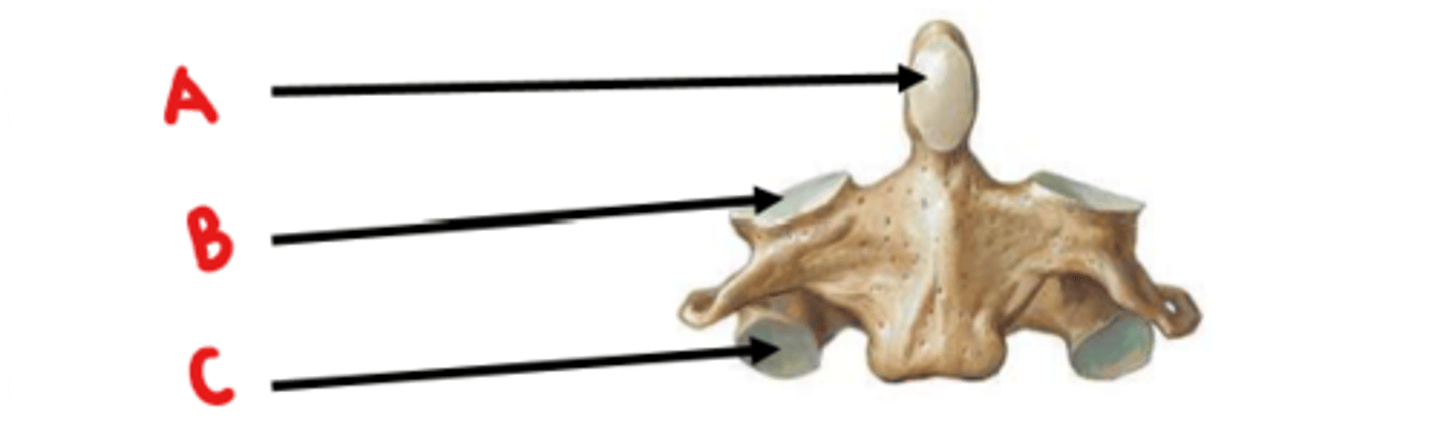

Axis (C2)

What vertebrae is this?

odontoid process (dens)

Identify A

superior articulating facet

Identify B

inferior articulating facet

Identify C